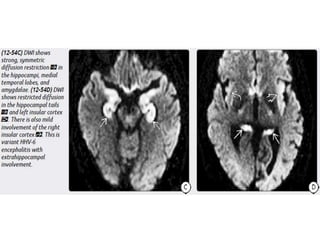

Herpes Simplex Encephalitis

HHV-6 Encephalopathy

Unlike childhood or adult HSE, neonatal HSV CNS infection is much

more diffuse. Both gray and white matter are affected.

Consider neonatal HSV encephalitis when cranial imaging at 2-3 weeks of

neonatal life

shows unexplained diffuse cerebral edema, with leptomeningeal

enhancement, without or with cerebral parenchymal hemorrhage.

Herpes Simplex Virus Imaging Unlikechildhood or adult HSE, neonatal HSV CNS infection is much more diffuse. Both gray and white matter are affected. Consider neonatal HSV encephalitis when cranial imaging at 2-3 weeks of neonatal life shows unexplained diffuse cerebral edema, with leptomeningeal enhancement, without or with cerebral parenchymal hemorrhage.